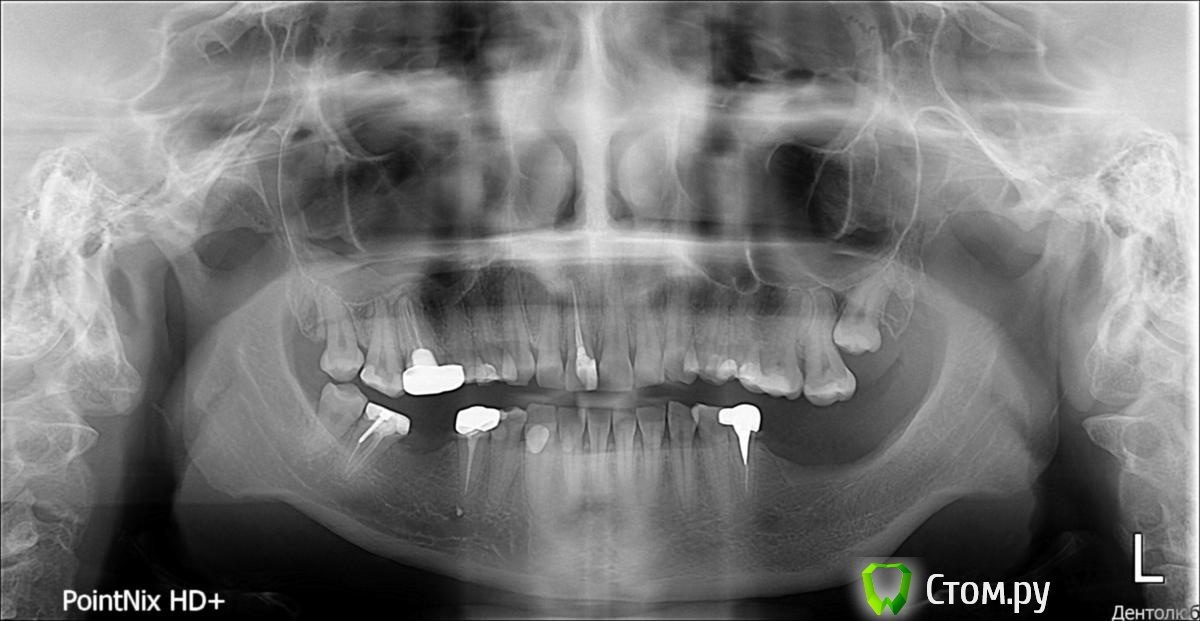

bibabo Опубликовано 4 февраля, 2014 Поделиться Опубликовано 4 февраля, 2014 Здравствуйте!До дальнейшей хирургической работы по остеопластике и имплантации мне предложили два варианта:1. Удаление всех восьмёрок. Они не мешают ни хирургии, ни ортодонтии, но это политика хирурга - презренным атавизмам во рту не место.2. Удаление только ретинированного 28 за то, что он ретинированный и у него плохие перспективы. Ссылка на комментарий

red_butler Опубликовано 4 февраля, 2014 Поделиться Опубликовано 4 февраля, 2014 если с 1.8 и 4.8 проблем нет, то убрал бы только 2.8 3 Ссылка на комментарий

IvanK Опубликовано 4 февраля, 2014 Поделиться Опубликовано 4 февраля, 2014 Если ортопед и ортодонт проблем не видят, то оставляйте. 28 на удаление. Ссылка на комментарий

Alexey Doc Опубликовано 4 февраля, 2014 Поделиться Опубликовано 4 февраля, 2014 Согласен , только 28 Ссылка на комментарий

SergioS Опубликовано 5 февраля, 2014 Поделиться Опубликовано 5 февраля, 2014 там за 28 скорее всего и 27 не далеко 1 Ссылка на комментарий